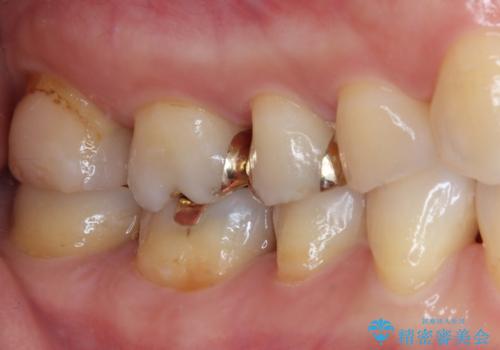

- 奥歯の銀歯をすべてゴールドにすることを希望された患者様です。

セラミックインレーによる補綴治療も提案しましたが、ご自身で強い咬合力を認識しており、歯にもインレーにもダメージの少ないゴールドインレーにて処置することとしました。